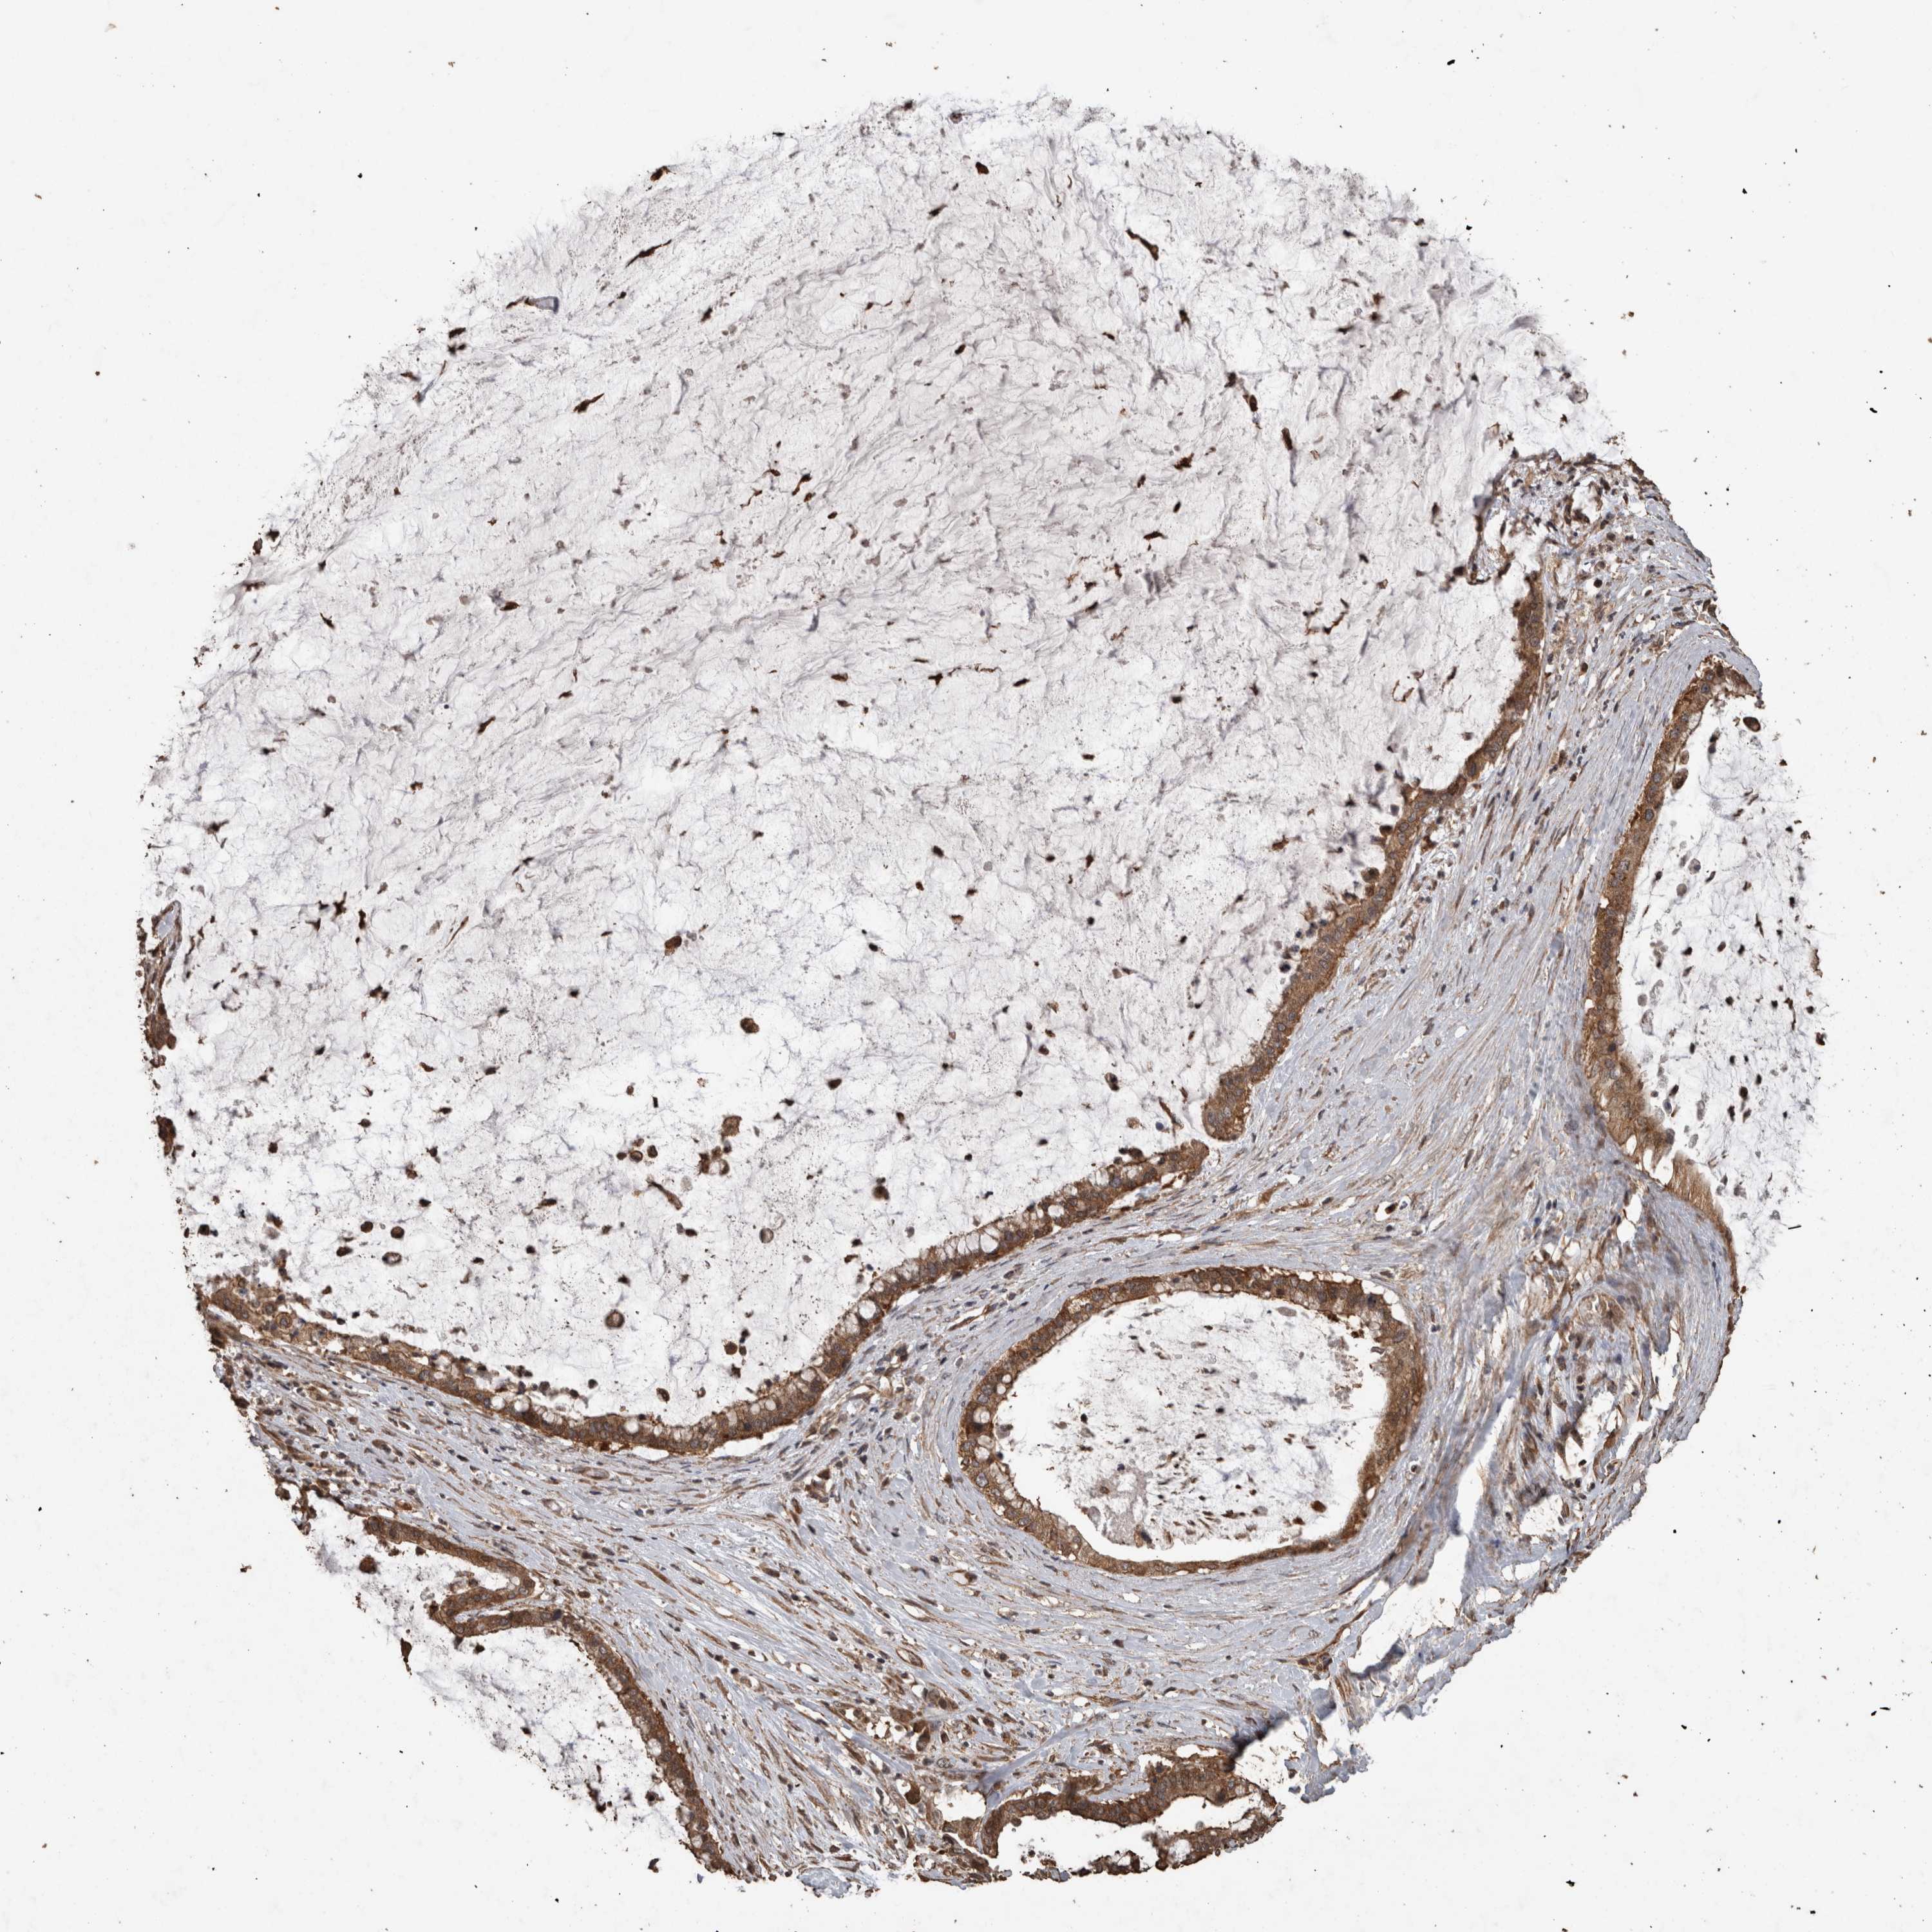

PANCREATIC CANCER - Protein expressioni

A mouse-over function shows sample information and annotation data. Click on an image to view it in a full screen mode. Samples can be filtered based on level of antibody staining by selecting one or several of the following categories: high, medium, low and not detected. The assay and annotation is described here.

Note that samples used for immunohistochemistry by the Human Protein Atlas do not correspond to samples in the TCGA dataset.

Antibody stainingi

Antibody staining in the annotated cell types in the current human tissue is reported as not detected, low, medium, or high, based on conventional immunohistochemistry profiling in selected tissues. This score is based on the combination of the staining intensity and fraction of stained cells.

Each image is clickable and will lead to virtual microscopy that enables deeper exploration of all samples and also displays staining intensity scores, fraction scores and subcellular localization as well as patient and tissue information for each sample.

Antibody HPA001931

Antibody CAB026191

Staining

High

Medium

Low

Not detected

Intensity

Strong

Moderate

Weak

Negative

Quantity

>75%

75%-25%

<25%

None

Location

Nuclear

Cytoplasmic/membranous

Cytoplasmic/membranous,nuclear

Adenocarcinoma, NOS